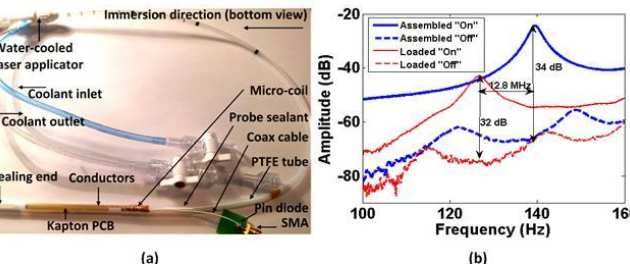

Evi Kardoulaki, Richard Syms, Ian Young, Marc Rea and Wady Gedroy

We have investigated whether local flexible micro-coils integrated with ablation catheters can improve the temperature accuracy during MR-thermometry in liver laser interstitial thermal therapies (LITTs). A liver-mimicking gel phantom was used to assess micro-coil derived image quality and sensitivity and ensure such coils can provide adequate FOV and resolution for the target application at 3T. The impact of liver motion was assessed using a MR-compatible hydraulic motion simulator. The thermal profile of a static phantom during an Nd:YAG laser ablation was monitored using reference-based PRF MR-thermometry and the robustness of the method under respiratory gating was evaluated on an un-heated phantom. The results were compared with the best locally available array coil for LITTs. Micro-coils improve the temperature accuracy by 1.5-10 times in a radius matching typical lesion dimensions and enable 1 mm image resolution. The resolution can be maintained during motion by using short acquisition time sequences while the SNR remains sufficient for accurate MR-thermometry. The temperature error on the un-heated phantom under respiratory gating does not exceed 1oC.

| a) Modified laser applicator with integrated micro-coil receiver and (b) S-parameters of the micro-coil tuned and matched for use in a 3T scanner. |

|